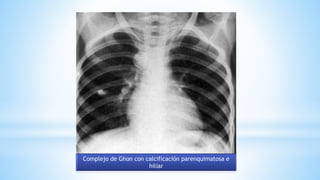

Complejo de Ghon con calcificación parenquimatosa e

hiliar